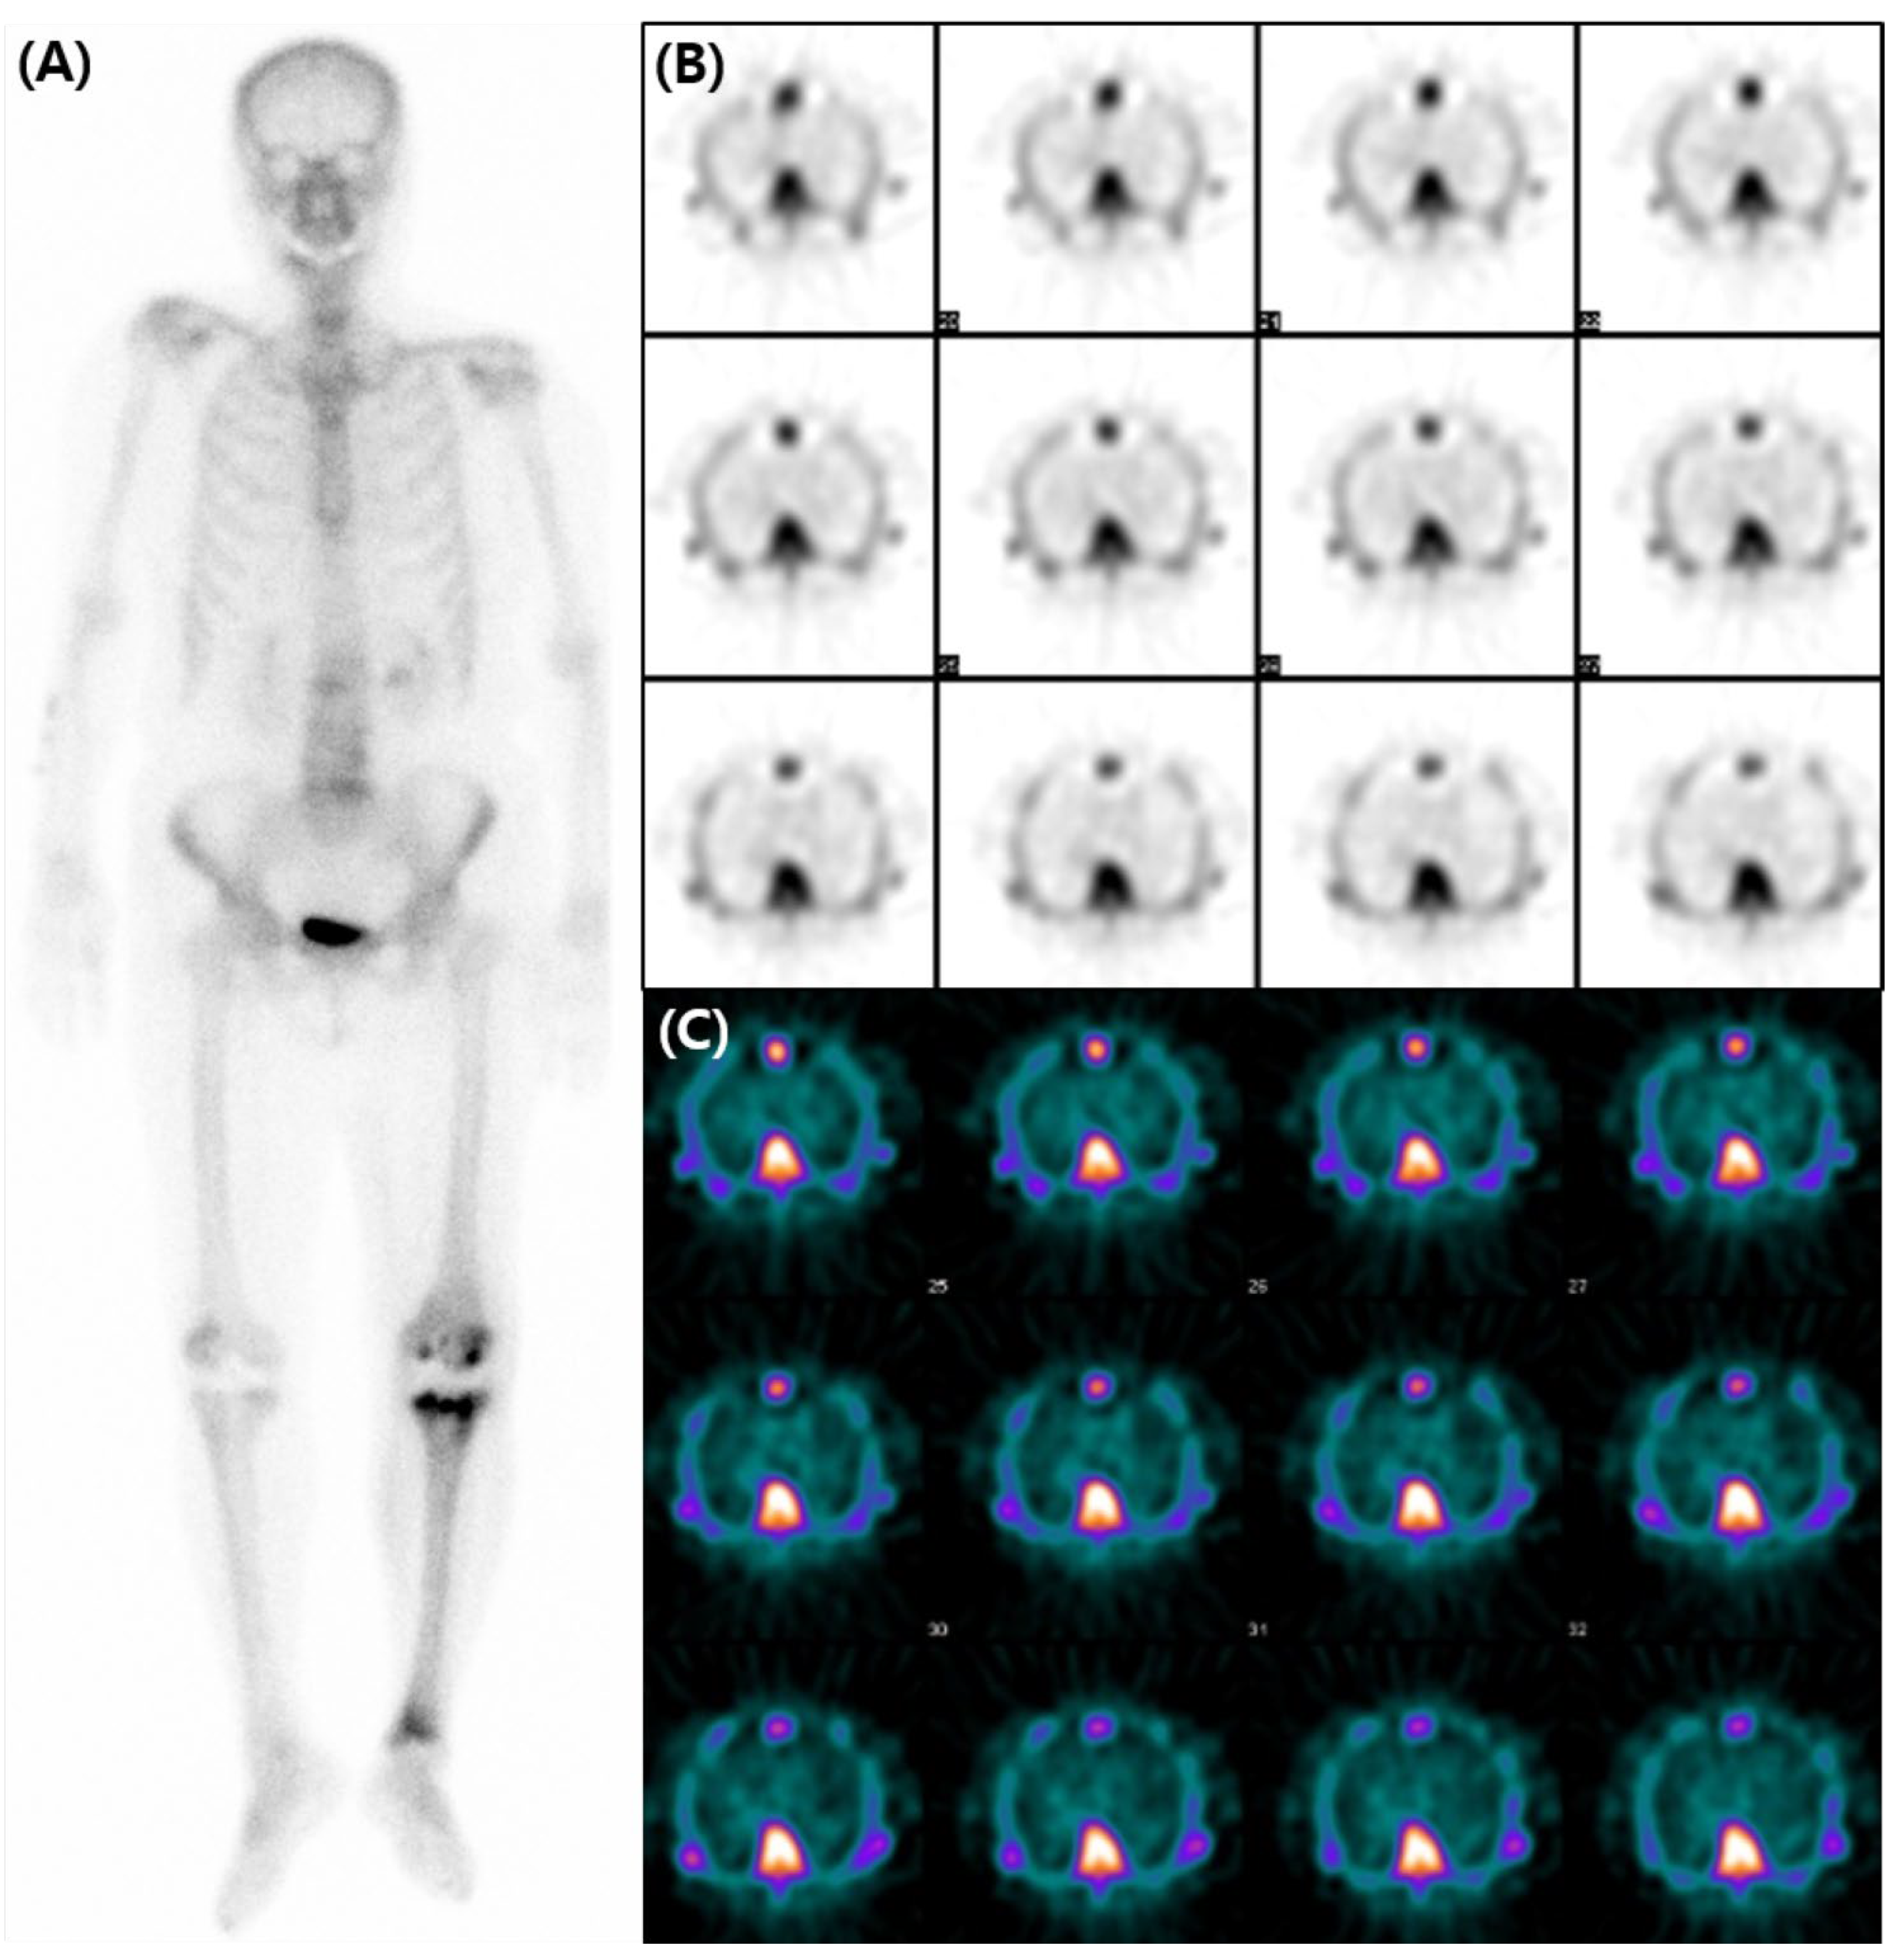

Diffuse Cardiac Uptake Misdiagnosed as Cardiac Amyloidosis in Bone Scan

Lee, Y.; Jang, J.; Na, S.J. Diffuse Cardiac Uptake Misdiagnosed as Cardiac Amyloidosis in Bone Scan. Diagnostics 2023, 13, 3342. https://doi.org/10.3390/diagnostics13213342